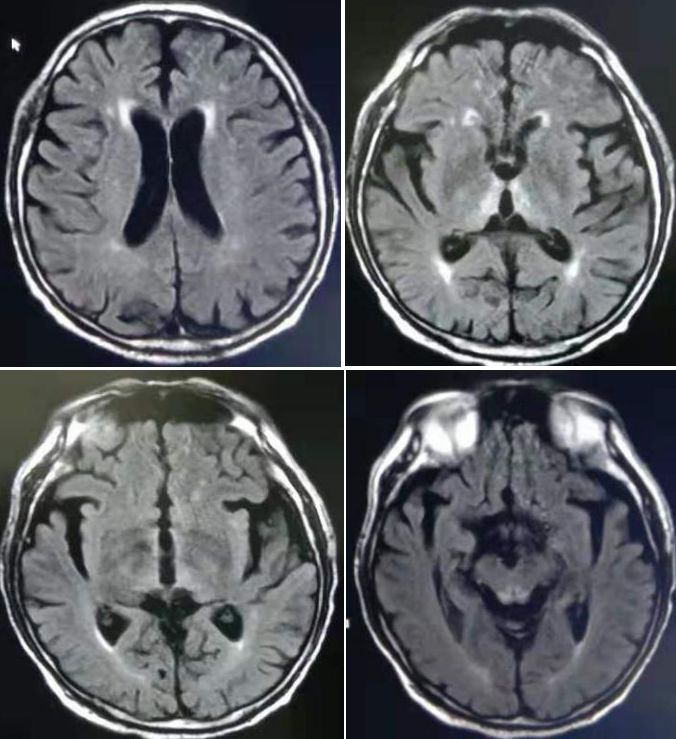

答案:韦尼克脑病。

本病例难度系数一般,临床上不罕见。患者既往有反复呕吐、纳差及饮酒病史,影像表现以乳头体、 第三脑室、 丘脑背侧核、 中脑导水管周围对称性分布的Flair高信号为主时均应想到本病。合并微出血是韦尼克脑病的另一特征,临床医生怀疑本病时应行SWI序列扫描,以与 NMO、低血糖脑病等进行更有效鉴别。